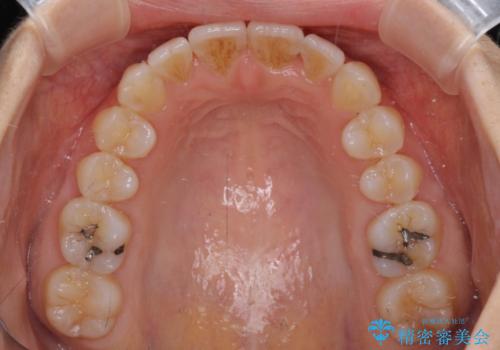

短期間で仕上げたい ワイヤーでの非抜歯矯正

上顎前歯の叢生が解消されると出っ歯になることが分かっていたので、両側奥歯付近にアンカースクリューを入れ、出っ歯を改善するためのゴムかけを行いました。

ゴムかけを頑張っていただいたので、当初の予定通り、1年強で治療を終えることができました。